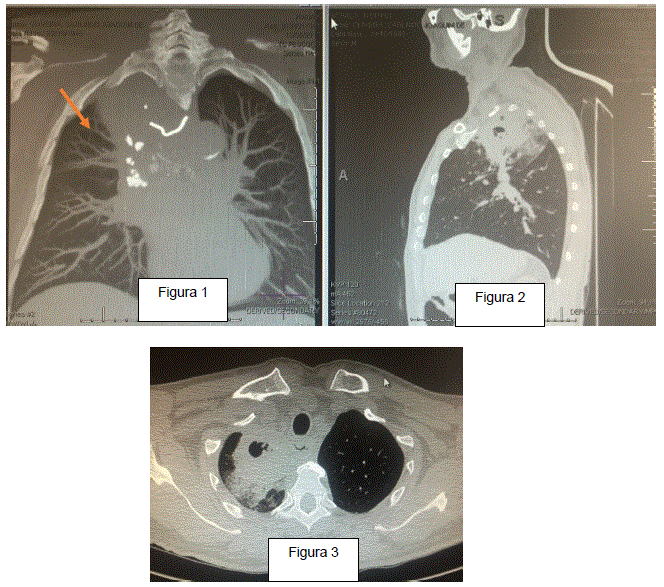

Homem, 73 anos, foi transferido de hospital secundário para avaliação em outro serviço de alta complexidade. Histórico de ingestão de corpo estranho (CE) há 40 dias durante refeição e desde então referia dificuldade para deglutir alimentos sólidos. Procurou vários serviços médicos que não fizeram diagnóstico correto. Há 10 dias começou a apresentar febre (Tax: 38,5º C) e expectoração purulenta. Antes da endoscopia digestiva alta (EDA) foi realizada tomografia de tórax (Fig.1 - 3) que identificou o CE assinalado na figura 1. A EDA foi realizada e constatado CE no 1/3 médio do esôfago que foi removido.

Paciente apresentava-se em bom estado geral, comunicativo, hidratado, descorado ++, eupneico. Tax: 36,8º C; Freq. Resp: 124 rpm; FC: 90 bpm; PA: 150 X 110 mmHg. SatO2: 93% (AA).

Com base nos dados clínicos e de imagem, quais são as medidas mais adequadas a serem adotadas a seguir?